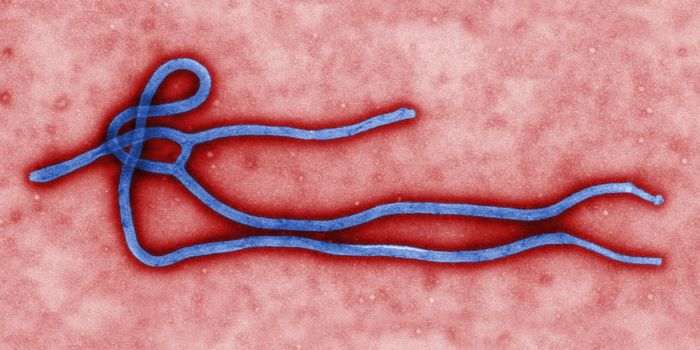

JAN 12, 2018InfographicsRemember ebola? The rare but extremely contagious and fatal virus that threatened to wipe out the world in 2014-2016? Ok ...